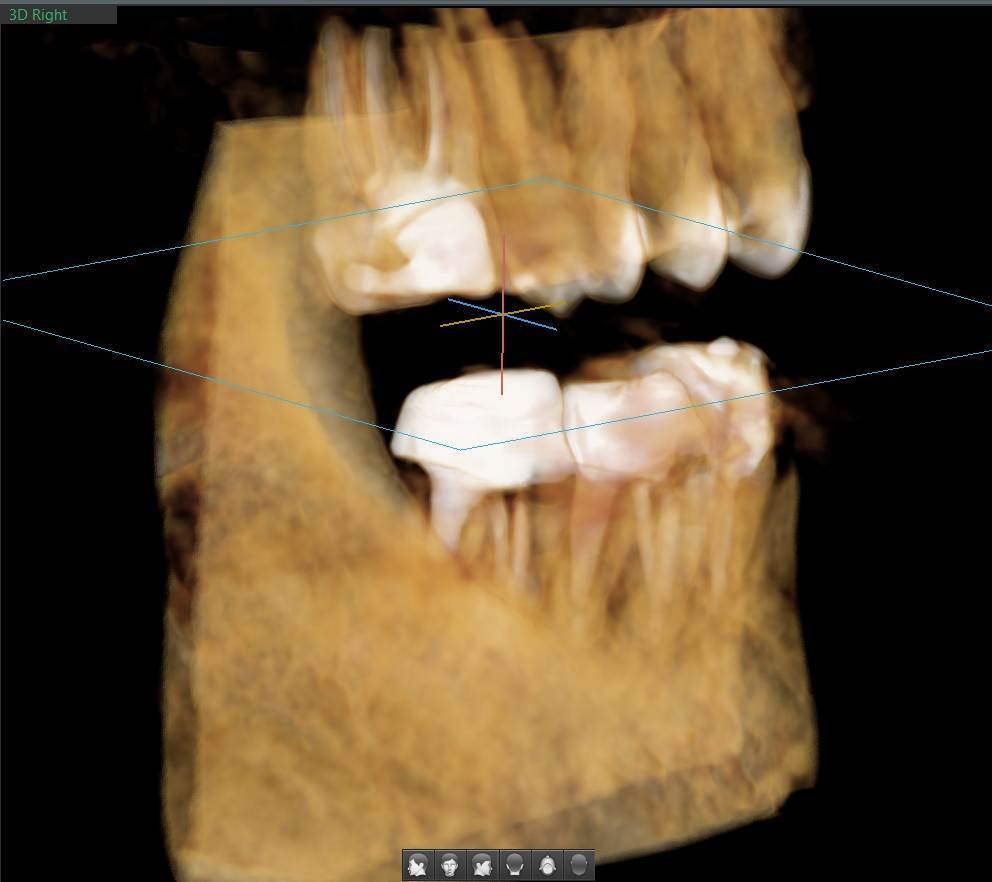

A-V-S Опубликовано 3 марта Поделиться Опубликовано 3 марта Здравствуйте. У меня такая ситуация: В начале января 2026 начал болеть зуб 7ка снизу слева - боль развивалась постепенно - в итоге стало больно жевать. Сделал КТ. Лечащий стоматолог сказал, что это проснулось спящее воспаление, перелечивать каналы зуба сложно - надо сверлить буром и доставать стекловолоконный штифт - надо удалять. В следующие дни открылся свищ и боль ушла. Свищ продолжает быть с периодическим набуханием и сдуванием после выброса гноя белого цвета. Этот зуб лечили с установкой стекловолоконного штифта чуть больше 5 лет назад. Посмотрите, пожалуйста, приложенные снимки и посоветуйте как быть - можно ли перелечить и сохранить зуб ? Ссылка на комментарий

АнтонТЛТ Опубликовано 3 марта Поделиться Опубликовано 3 марта Добрый вечер, лучше выложить несколько срезов этого зуба, либо архив с кт. По представленным снимкам, есть подозрение о наличии трещины между корнями зуба. 1 1 Ссылка на комментарий

Гарриевич Опубликовано 6 марта Поделиться Опубликовано 6 марта Не знаю обрадует Вас это или огорчит, но зуб можно сохранить соседний тоже с воспалением кстати 1 1 Ссылка на комментарий

A-V-S Опубликовано 9 марта Автор Поделиться Опубликовано 9 марта @Гарриевич , @red_butler . спасибо. В 06.03.2026 в 21:28, Гарриевич сказал: соседний тоже с воспалением кстати @Гарриевич , на соседнем свища нет. Тоже надо перелечивать вместе с 7 ? Ссылка на комментарий

Doc Опубликовано 10 марта Поделиться Опубликовано 10 марта 16 часов назад, A-V-S сказал: на соседнем свища нет. Тоже надо перелечивать вместе с 7 ? Отсутствие свища не снимает проблемы наличия кисты на этом зубе. Рано или поздно будет вам свищ, либо зуб так заболит, что придется удалять безо всякого свища. 1 Ссылка на комментарий